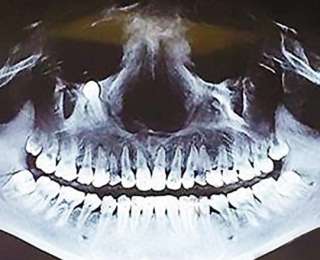

Китайские хирурги удалили трёхсантиметровый зуб, который пророс сквозь стенку глазницы 28-летней девушки, сообщают китайские СМИ. Операция была проведена в городе Чунцин.

Обратившись к врачам, девушка была шокирована. Оказалось, что причиной боли в глазу был прорастающий снизу зуб. Хирурги попросили Цао Фан не медлить и сразу провести операцию, так как зуб мог сильно повредить глаз девушки. К счастью, хирургическое вмешательство прошло успешно, и зуб был удалён.